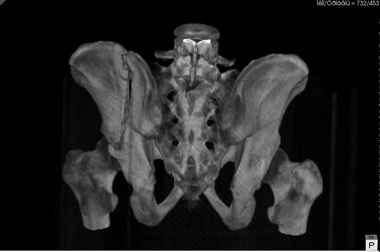

Удобнее всего будет подвздошно-паховый доступ, который даст возможность на всем протяжении расчистить костно-хрящевые разрастания и проконтролировать полость сустава. Фиксация 2-мя реконструктивными пластинами: а) по лонной кости вдоль терминальной линии до внутренней подвздошной ямки; б) короткая пластина на 4-5 отверстий вдоль гребня подвздошной кости (проще будет ставить снаружи).

Уважаемые коллеги! В даном конкретном случае речь идет о "ложном суставе", поэтому показано реконструктивно-восстанвоительная операция т.е. остеотомия по линии "ложного сустава" затем остеосинтез реконструктивными пластинами, мы выбрали пахово-подвздошный (с наружным) доступ т.к. линия излома проходит на крышу вертлужной впадины. С уважением Ерсин Жунусов

Уважаемый Андрей!Исходя из данных КТ смещение не критичное (пациент ходит, головка "не истерлась и не рассосалась",беспокоит болево синдром.стабилизируйте поврежение из доступа,которым владеете лучше. в данном случае равноценны подвдошнопаховый и кохера-лангенбека с доплнительным окном по гребню. фиксация реконструкционными пластинами либо тазовыми винтами "Synthes".желаю успеха! Ушаков.

Равноценными быть не могут. При передней колонне доступ Kocher-Langenbeck не показан.

О какой реконструкции свода идет речь? опорная часть впадины сохранена,гловка в полном объеме, кистозная перестройка, скорее всего проявление иммобилизационного остеопороза.29 лет не пугает возраст для эндопротезирвания, да еще с сеткой где максимум пара трения полиэтилен /керамика 15-17 лет. отсеосинтез, соглашусь с коллегами подвздошнопаховый доступ, динамическое наблюдение, эндопротезрование только в случае аваскулярного некроза,б/цементной чашкой с парой тения керамика/керамика. желаю успеха! Всех с рождеством! Ушаков.